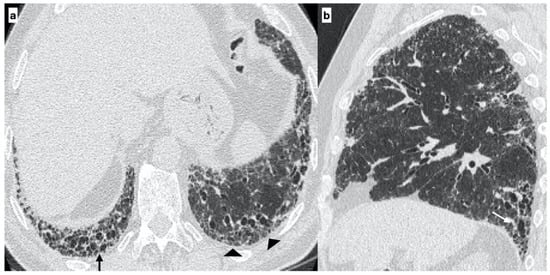

At diagnosis, there was a statistically significant difference in the HRTC pattern between the two groups: sporadic IPF patients had a predominantly typical UIP pattern compared to familial IPF patients (60.0% vs. 21.1%, respectively). There was a predominance of an alternative diagnosis HRTC pattern in familial IPF compared to sporadic IPF (31.6% vs. 2.2%, respectively) (see Figure 1, Figure 2 and Figure 3). The HRCT for 6/19 patients with a familial pulmonary fibrosis at the onset of symptoms had an alternative diagnosis pattern: this was due to the presence of a fibrotic nonspecific interstitial pneumonia (NSIP) pattern in 4/19 patients, whilst in 2/19 patients it was due to the presence of honeycombing with upper-mid lung distribution (see Figure 1). At the onset of symptoms, only 1/46 sporadic IPF patients had an alternative diagnosis HRCT pattern, due to the presence of honeycombing with upper-mid lung prevalence and mosaic attenuation; the definitive diagnosis of IPF was made by biopsy (see Figure 2 and Figure 4). After 2 years from diagnosis in the familial IPF group, we observed a slight increase in the typical UIP pattern at HRTC evaluation (see Figure 3 and Figure 5).

Figure 1. A 29-year-old female with an “alternative diagnosis pattern” on HRCT at onset of respiratory symptoms. The axial HRCT image shows the presence of honeycombing (black arrows), reticulations (arrowheads) and traction bronchiectasis/bronchiolectasis (white arrows) with a prevalent upper-mid lung distribution (a). The sagittal plane better evidences the atypical distribution of fibrotic alterations (b). Genetic analysis demonstrated the following mutations: ABCA3, SFTPA2, promoter-TERT, SFTPC.